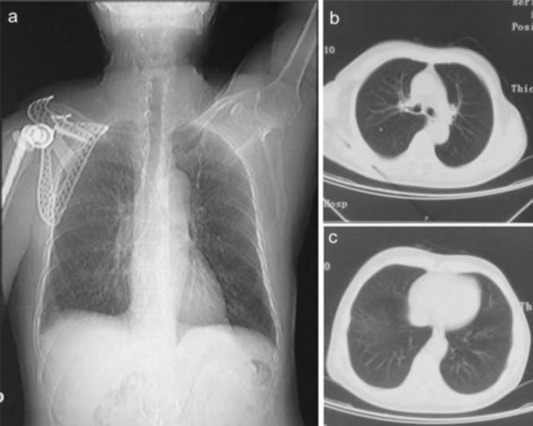

An artificial total shoulder was customized, and the operation of the right scapular tumor resection and tumor type with to wholly the scapula artificial shoulder arthroplasty and lesions lymph node including the pathological lymph node below right subclavian and above left supraclavicular dissection had been performed in March 2011 (Fig. 4 a, b). To achieve full exposure of scapular and tumor, scapular notch was implemented, approximately 2 cm of the distal end of right clavicle excised. Then the original tumor and the 3 cm area surrounding it together with whole right acromioclavicular joint was removed, followed by fixing biceps long head tendon to stump of clavicle and prosthesis installment. After discharge from our hospital, ten days of chemotherapy, combination of dacarbazine, pharmorubicin and cisplatin, was applied in patient in May 2011 in another hospital and given up due to anorexia and vomit. Right scapular mass, right submaxillary lymphadenectasis, and ascites were observed. Nodules in superior lobe of right lung and inferior lobe of left lung were observed in CT results (Fig. 5 a, b, c) which suggested potential pulmonary metastases in September 2011. Multiple organ failure caused the death of patient in November 2011.

Fig. 4. Postoperative X-ray test. Images show that shoulder joint prosthesis is well placed. |

Fig. 5. CT images show nodules in superior lobe of right lung and inferior lobe of left lung. |